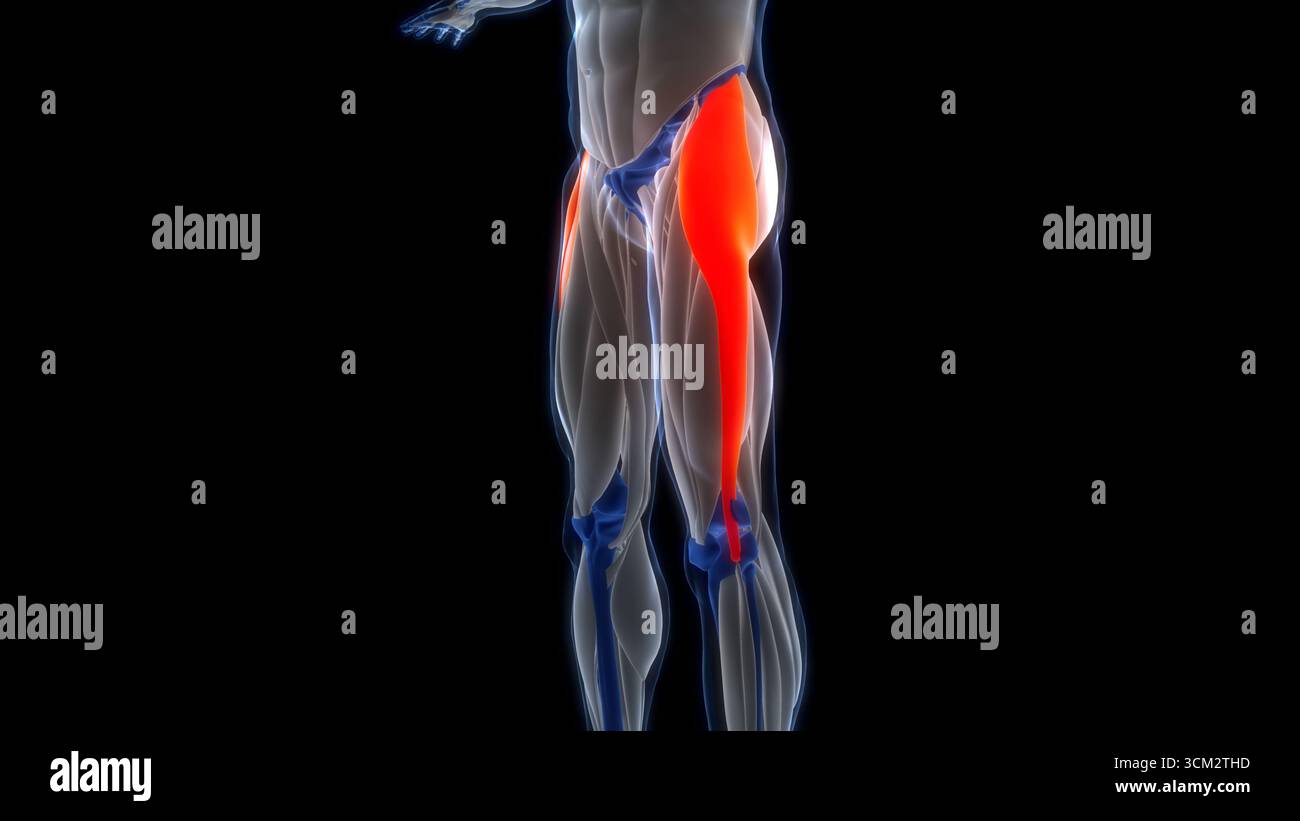

Human Muscular System Leg Muscles Tensor Fasciae Latae Muscles Anatomy Stock Photohttps://www.alamy.com/image-license-details/?v=1https://www.alamy.com/human-muscular-system-leg-muscles-tensor-fasciae-latae-muscles-anatomy-image700771049.html

Human Muscular System Leg Muscles Tensor Fasciae Latae Muscles Anatomy Stock Photohttps://www.alamy.com/image-license-details/?v=1https://www.alamy.com/human-muscular-system-leg-muscles-tensor-fasciae-latae-muscles-anatomy-image700771049.htmlRF3CM2THD–Human Muscular System Leg Muscles Tensor Fasciae Latae Muscles Anatomy